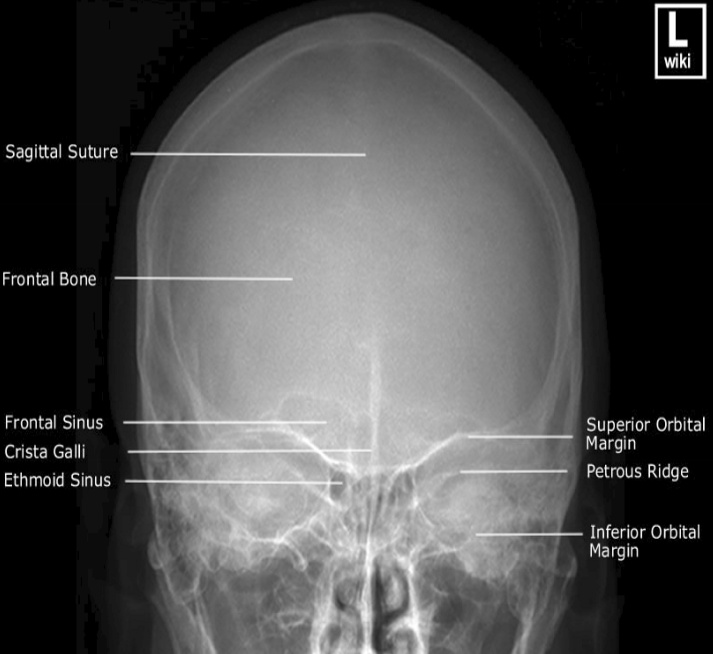

Please label